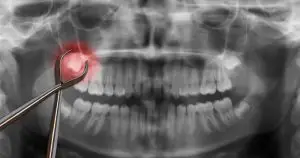

Tooth Extraction ProcessAs dentists, we try to save damaged teeth when possible, but there are times when this isn’t an option. In these cases, an extraction will be recommended to prevent severe damage or decay or to lower the risk of infections. If you need a tooth removed due to serious decay or for other reasons, knowing what happens can help you feel less nervous about the procedure.

The steps involved in a tooth extraction depend on whether you need a simple or surgical removal done. A simple extraction involves numbing the area before loosening your tooth and removing it using dental forceps. During this procedure, your dentist typically does not have to make any cuts or incisions in your gums.

If you need a surgical extraction, such as when a tooth that hasn’t completely grown in, this procedure is a bit more complex. Surgical extractions involve having a tiny incision made in your gum in order to get to the affected tooth and remove it. This can also involve having multiple teeth removed during one visit. For example, removing three or four impacted wisdom teeth.